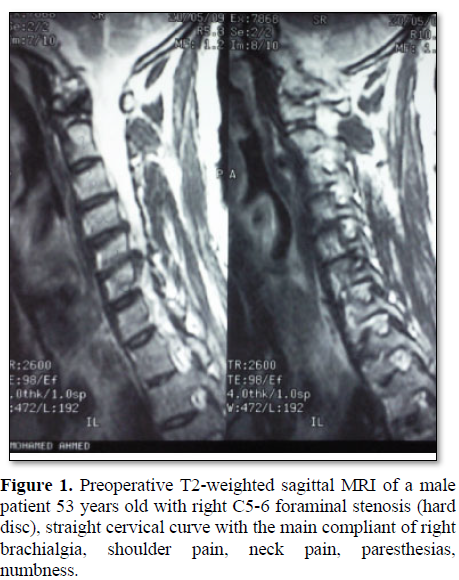

Cervical radiculopathy is a clinical diagnosis defined by the presence of sensory or motor deficits caused by mechanical compression of the corresponding cervical nerve root. Degenerative etiologies include disc herniation, spinal canal stenosis and spondylotic foraminal stenosis [1] (Figure 1). Cervical radiculopathy caused by posterolateral disc herniation can be managed by either an anterior or a posterior approach. The posterior approach was originally reported by Mixter and Barr [2]. The keyhole posterior foraminotomy was described by Spurling and Scoville [3].

The posterior laminoforaminotomy preserves cervical range of motion minimizes adjacent segment disease [4]. The conventional anterior cervical approaches use the surgical plane between medially trachea and laterally great vessels (carotid and jugular vein); and view the spine almost in face. These approaches can be called as anteromedial approach. On the other hand, anterolateral cervical foraminotomy approach retracts the great vessels medially, uses a more lateral angle of view, and views the spine obliquely [2,5-8] (Figures 2 and 3).